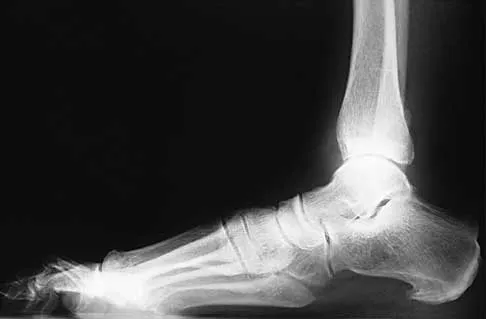

A 57-year-old man has had right ankle pain for the past 10 months following an injury that went untreated. Radiographs are shown in Figures 30a through 30c. Management should consist of